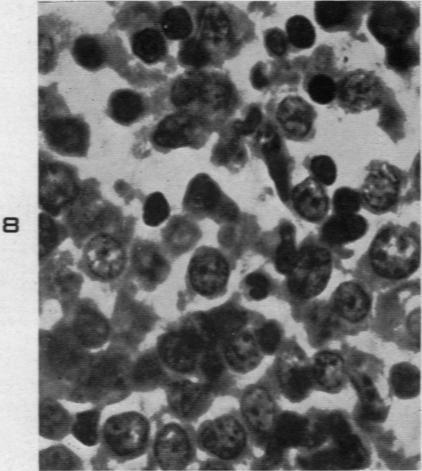

Malignant Lymphoma (So-Called Leukemia) in Dogs.

Am J Pathol. 1945 Jul;21(4):683-715.